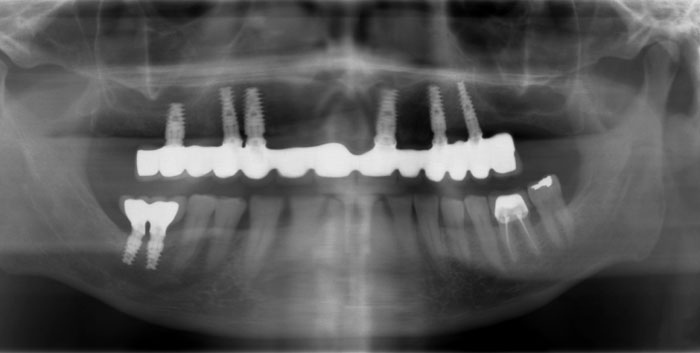

CAS N°2 Bridges sur 6 implants dentaires DIO mâchoire supérieure. La 1ère étape à consisté à extraire les 7 dents restantes et à poser une prothèse provisoire amovible. Quelques mois plus tard pose de 6 implants DIO et 3 mois plus tard la pose du bridge sur implant.

Europa Dental Hongrie